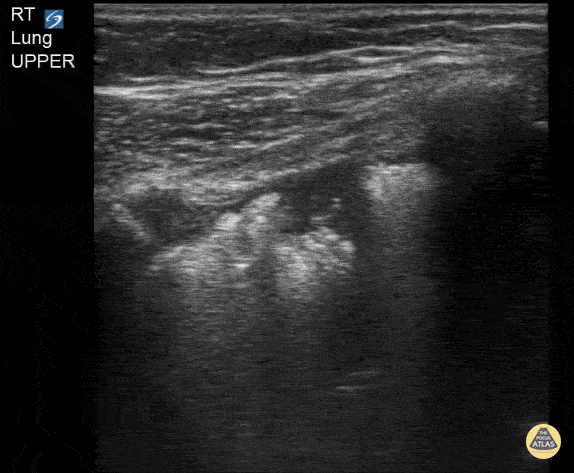

Peds-Lung - Subpleural Consolidation in 3 Year Old

3 y/o with respiratory distress. Found to have a large subpleural consolidation on CXR. Contributor: Kathryn Pade, MD, Rady Children's Hospital San Diego